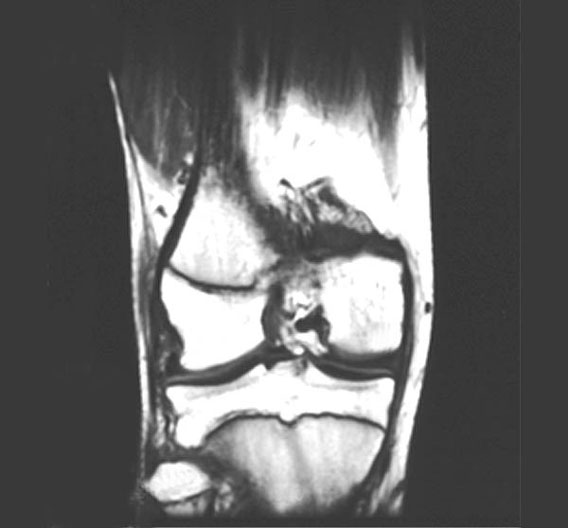

Knee MRI-Coronal View

1. Lateral condyle of femur

2. Articular cartilage

3. Lateral condyle of tibia

4. Fibula

5. Medial condyle of femur

6. Articular cartilage

7. Medial condyle of tibia

8. Epiphyseal plate of tibia